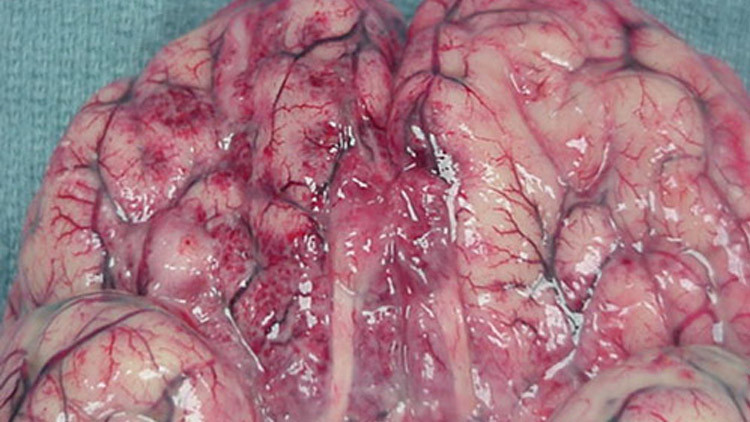

طفيليات الأميبيا آكلة الدماغ تثير رد فعل مناعي قاتل

تتمكن الأميبيا من التوغل الى داخل دماغ الإنسان أو الحيوان وتبدأ بأكله من الداخل.

تعيش أميبيا من نوع “Naegleria fowleri ” عادة في المياه العذبة في كافة أنحاء العالم وتتغذى على البكتريا. إذا سبح الإنسان أو أي حيوان ضخم في مياه تعيش فيها هذه الأميبيا، يمكن ان تدخل جسمه عبر الجهاز التنفسي، وتحاول التقرب من الدماغ بحثا عن الغذاء. وفي حالة وصول هذه الأميبيا الى الدماغ فإنها تبدأ بتدمير الأنسجة القريبة وأكل الخلايا وطرح بروتينات خاصة تسبب دمار الخلايا الأخرى.

من جانبها تبدأ منظومة المناعة في جسم الأنسان بهجوم معاكس، حيث تغرق الدماغ بخلايا المناعة، مما يسبب ظهور التهابات وخزب (استسقاء) الدماغ. أي ان المناعة لا تخدم الجسم في هذه الحالة، بل تعمل ضده.

لا يوجد حاليا أي علاج لهذه الحالات. ولكن قبل فترة اقترح أطباء من الولايات المتحدة القضاء على الأميبيا بواسطة المستحضر المستخدم في علاج داء الليشمانيات “Leishmaniasis”. وقد برهن الباحث الباكستاني منان وفريقه العلمي ان الموت لا يحدث بسبب توغل هذه الأميبيا الى الدماغ، بل بسبب رد فعل مناعة الجسم على وجودها في الدماغ.